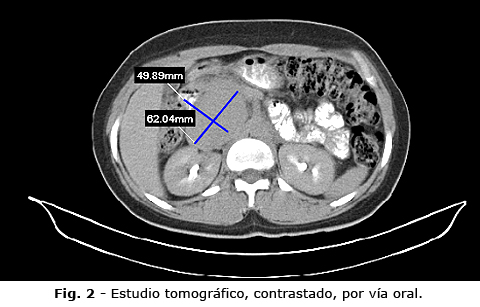

Luego se realizó una segunda exploración, con empleo de contraste intravenoso (Fig. 3). Se informó la presencia de una imagen nodular epigástrica, con ligero realce del contraste, de características heterogéneas, con densidades que oscilan entre 73 a 95 UH, medía aproximadamente 56 mm x 55 mm x 71 mm, de contornos bien delimitados, regulares, que provoca desplazamiento de la vena cava inferior, vena porta, cabeza e inicio del cuerpo de páncreas y cercana a la aorta; contacta con el pilar del diafragma. El resto del estudio del hemiabdomen superior e inferior no tenía datos nuevos.